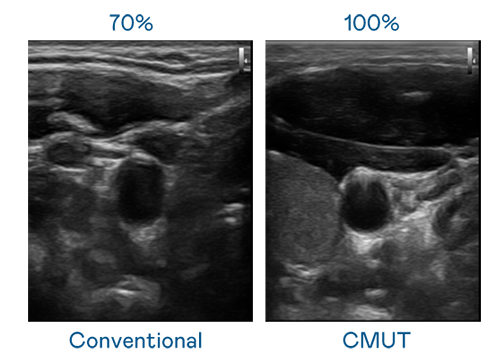

CMUT 技术是一种用电容式微机电元件来产生超音波讯号的技术。与传统 PZT 压电式技术相比,CMUT 频宽增加 30%,更宽频的超音波讯号让影像解析度大幅提升,是实现高影像品质医疗超音波扫描、促进精准医疗发展的关键技术。

大频宽带来超清晰影像

超音波影像的解析度高低,首先取决于探头能发出的讯号频宽。evo视讯 CMUT 可提供高清晰的超音波讯号,提供高频宽、高灵敏度、影像纹理细节更高的超音波影像,协助医护人员缩短影像判读时间及利用精准的医疗影像进行诊断。